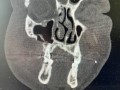

Rozległa torbiel zawiązkowa żuchwy

Paulina Adamska, Maria Mikołajska, Anna Janowska, Anna Starzyńska